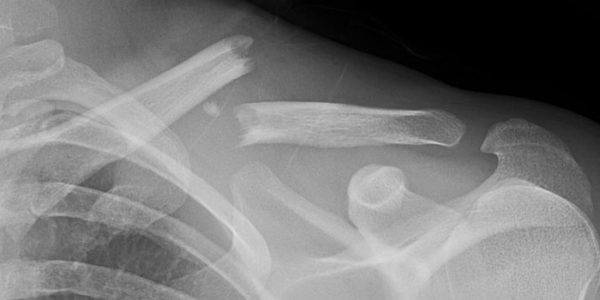

Clavicle (collarbone) fractures are typically categorized as either proximal (closer to the midline of your body), midshaft, and distal (closer to your shoulder). The majority of these fractures can be treated by wearing a sling while the bone heals. Sometimes, if the bones have moved too far apart, then you may need surgery to realign the bones.

Evaluation by your provider will include x-rays and physical exam to determine if there is a fracture present, and to help guide treatment.

Surgical: If your bones are too far apart to heal properly, or if the fracture is too close to the joint-then you are more likely to need surgery. Surgery most commonly involves an open incision to realign the bones back to their normal position. A metal plate and screws are then applied to hold the bones in place while they heal.